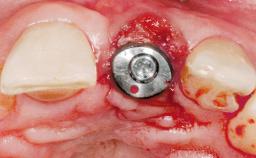

Immediate Flapless Placement of an Implant in a Maxillary Right Lateral Incisor Site

This 43-year-old male patient, a non-smoker, came to our practice because of a fracture of tooth 12 caused by a bicycle accident. Due to the combined para- and infrabony crown and root fracture, tooth extraction, and subsequent implant placement were suggested to the patient as the therapy of choice. The patient had high esthetic expectations with regard to the treatment outcome and asked for an immediate fixed provisional restoration. His individual esthetic risk profile summed up to a medium esthetic risk.

Placement Protocol Immediate implant placement

Tooth Site Maxillary incisor or canine

Loading Protocol Immediate